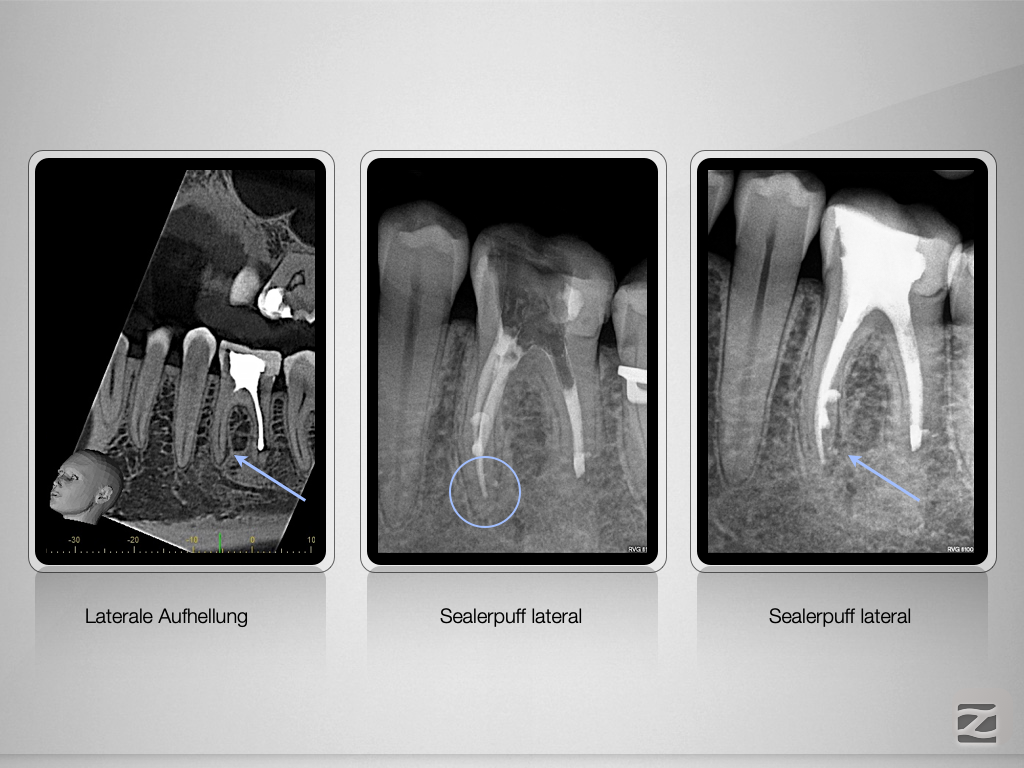

36D.010